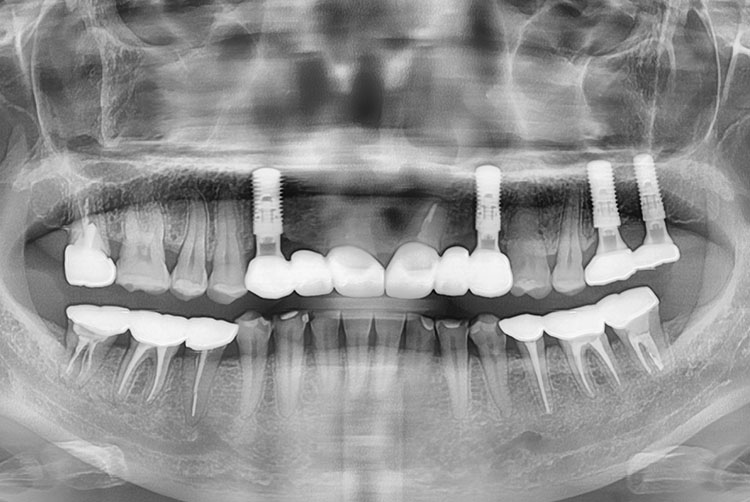

[임플란트] 임플란트

7a31e411748c41fece11c9bd0f0f12f2.jpg

치료전 : 2018-03-16